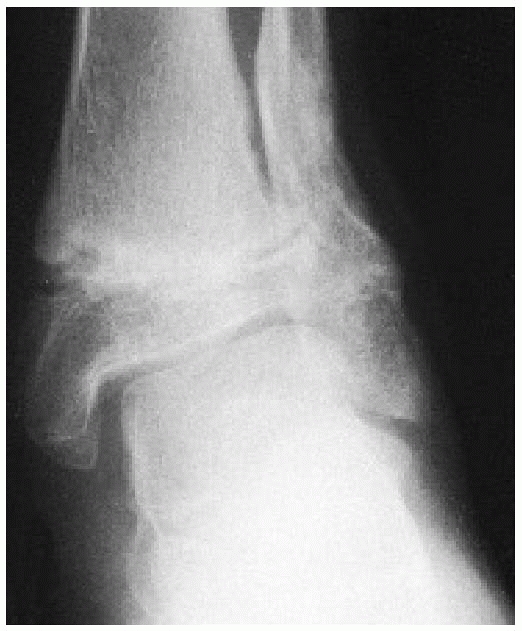

FIGURE 26-33 A. Severely displaced pronation-eversion-external rotation injury. B.

Closed reduction was unsuccessful, and a valgus tilt of the ankle mortise was noted. At surgery, soft tissue was interposed laterally (arrows). C. Reduction completed and stabilized with two cancellous screws placed above the physis. |

tibial physis during closed reduction, many authors recommend the use